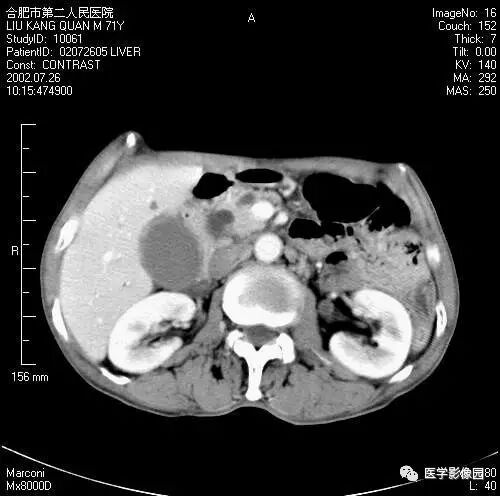

图6-4-16胰腺癌

A. 增强扫描见胆总管扩张(↑),

胆囊扩大,左肾有两个小囊肿;

B.(与A图间隔5mm的层面)扩张的总胆管

突然中断、消失,钩突部见低密度肿块